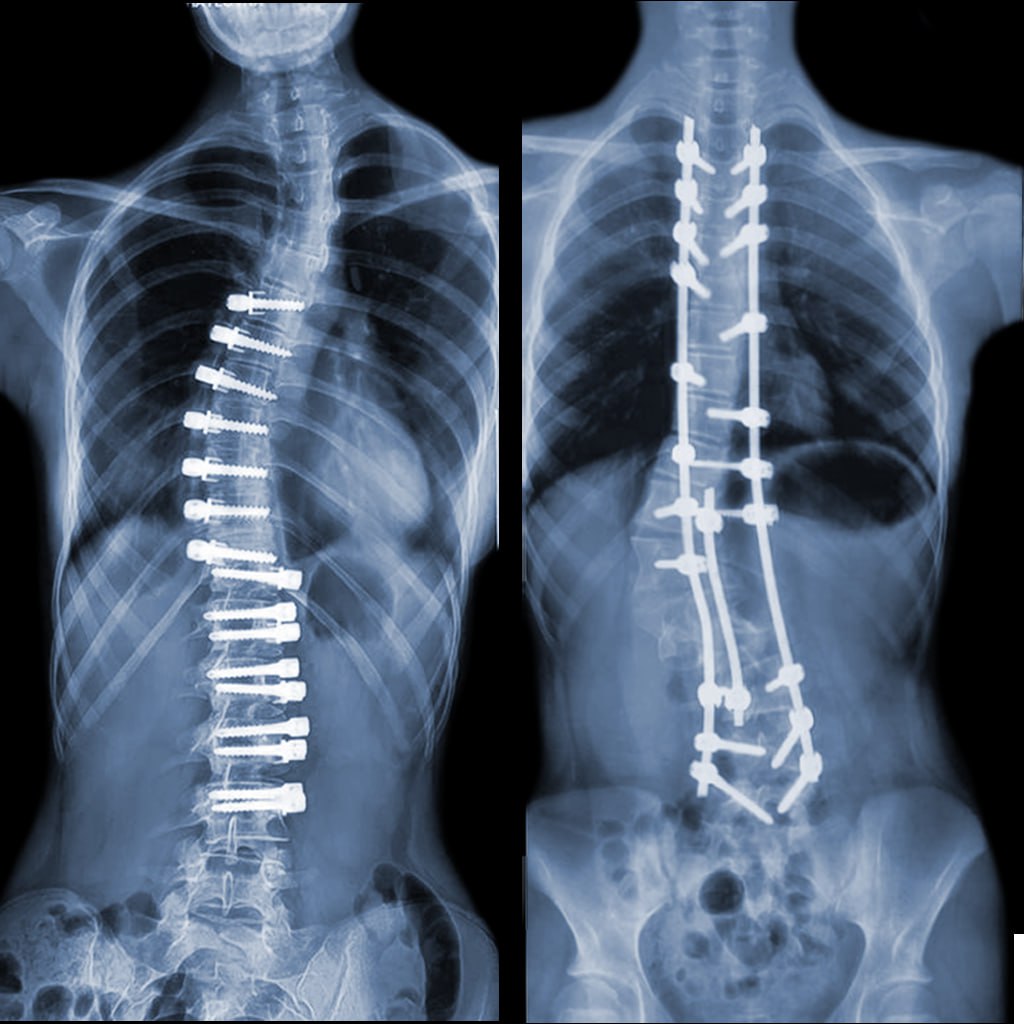

Различия ригидной (классической транспедикулярной) и динамической систем коррекции сколиоза

Ригидная система

Операционный доступ: передний или задний

Цель: коррекция деформации и формирование спондилодеза (сращение позвонков между собой)

Механизм коррекции: позвоночник фиксируется жёсткими винтами, стержнями и удерживается в правильном положении

Динамическая система

Операционный доступ: боковой или эндоскопический

Цель: коррекция деформации и сохранение подвижности позвоночника

Механизм коррекции: позвоночник фиксируется с помощью винтов и гибких кордов с определённым натяжением

Наглядное сравнение динамической и ригидной систем коррекции сколиоза через 3 месяца после

операции.